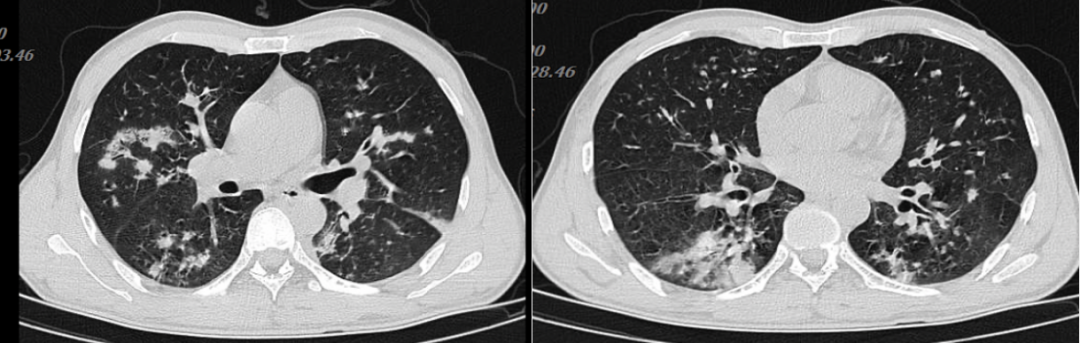

三、相似病例

病例1,男性,42岁,浙江衢州务工,油漆工,既往体健。发热半月,伴全身酸痛,咽痛,体温39℃,咳嗽,咳黄痰,当地医院拟“肺炎”住院,予抗感染治疗后无好转,转至我院,拟“社区获得性肺炎”于2023年4月7日收住。甲型流感合并气管支气管曲霉病。

图片

病例1胸部CT

病例2,女性,39岁,肾移植术后7个月。因“发热1周、呼吸费力伴声音嘶哑2天”于2024年1月14日入院。最终诊断为乙型流感合并气管支气管曲霉病。

病例2胸部CT

2020年发表的一部多国专家共识认为IAPA有两种类型,一种是气管炎型,另一种是肺曲霉病型。气管炎型IAPA在气管镜下可见明显的白斑、溃疡表现,肺部影像学可不明显,也可以有,合并粒缺或肾移植等有宿主免疫抑制患者更易出现肺部实质空洞、晕征、大片实变等。健康宿主气管炎型IAPA的肺部影像学表现可能不明显。肺曲霉病型IAPA表现为肺组织结节影、空洞影、月牙征。曲霉病的治疗药物和疗程非常关键,但如何发现曲霉感染也是提高救治成功率的重要问题。通常我们的疗程是3个月,第1个月进行静脉诱导,如果诱导成功,之后的2个月序贯口服

上述3个病例代表了3种不同的IAPA类型。第一例患者是相对健康的成人,是重症甲流合并气道曲霉感染。第二例患者是正常成人气管支气管曲霉感染。影像学也有曲霉侵袭的表现。第三例患者是免疫抑制宿主,乙流合并侵袭性肺曲霉病。对于免疫抑制宿主,疗程会更长,至少要达到临床症状缓解、肺部吸收基本仅余瘢痕,气管镜检查气道黏膜干净,并且免疫抑制状态得到一定的缓解。对于免疫功能相对正常患者,需要达到肺部/气道病灶缓解。普通病房的慢阻肺患者如果合并IAPA,我们一般会坚持用药1个月,待患者整体症状明显缓解,并且肺内也无侵袭性表现